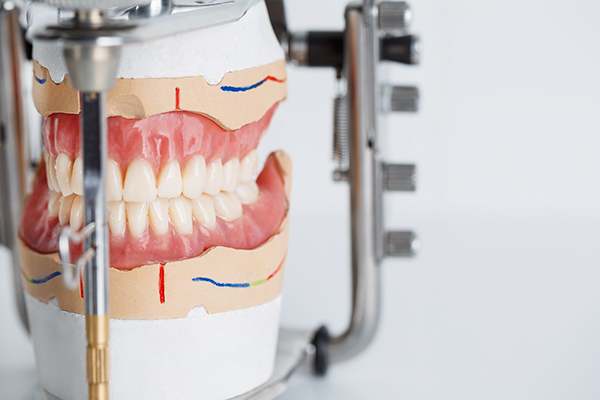

かみ合わせにこだわって製作

入れ歯でしっかり噛めるようにするには、まず「かみ合わせ」が合っていることが絶対条件です。型採りが精密なのは当然のことですが、それ以上に重要なのが「咬合採得」、つまりかみ合わせの記録です。ここを誤ると、どれだけ精密に作っても、最終的に噛みにくい・外れやすい・痛いといったトラブルにつながり、結果として使わなくなってしまいかねません。そうならないためにも、当院ではかみ合わせの再現にこだわって、長く使える入れ歯をお作りしています。